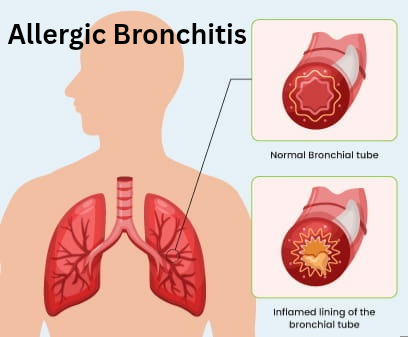

Are you feeling shortness of breath, coughing & wheezing? Allergic Bronchitis is a respiratory condition where allergens trigger inflammation in the bronchial tubes, leading to symptoms like coughing, wheezing, shortness of breath, and chest tightness. In this article, we’ll explore how homoeopathy offers a personalized and comprehensive approach to treating allergic bronchitis, focusing on root cause, symptom relief, and overall well-being through natural remedies and lifestyle changes.

Recognizing Symptoms of Allergic Bronchitis :

– Persistent coughing, often worse at night or early morning

– Wheezing or a high-pitched sound while breathing out

– Shortness of breath or difficulty breathing

– Chest tightness or a feeling of pressure in the chest

– Excessive mucus production, which may be clear, yellow, or greenish